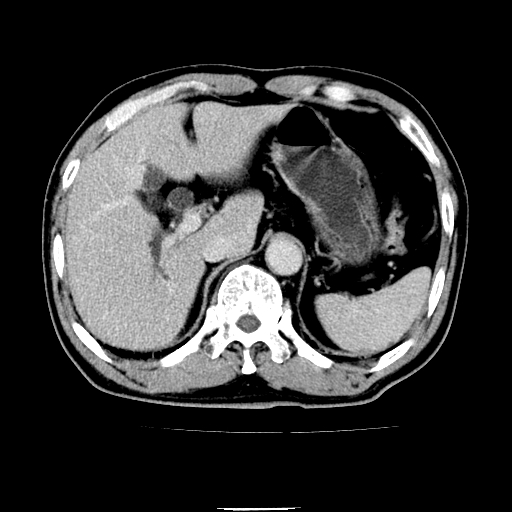

以下是引用chenqiong在2010-3-25 20:56:00的发言:[br]1、胆囊炎,胆囊息肉[br]2、肝内胆管及胆总管扩张,胆总管下端结石[br]3、十二指肠乳头旁憩室

以下是引用zxl51642在2010-3-26 10:47:00的发言:[br]胆囊炎,胆囊息肉,胆总管扩张,但未看到明显肿块,肝内胆管扩张不像恶性,炎性狭窄或阴性结石可能吧,建议mrcp,右肾小囊肿